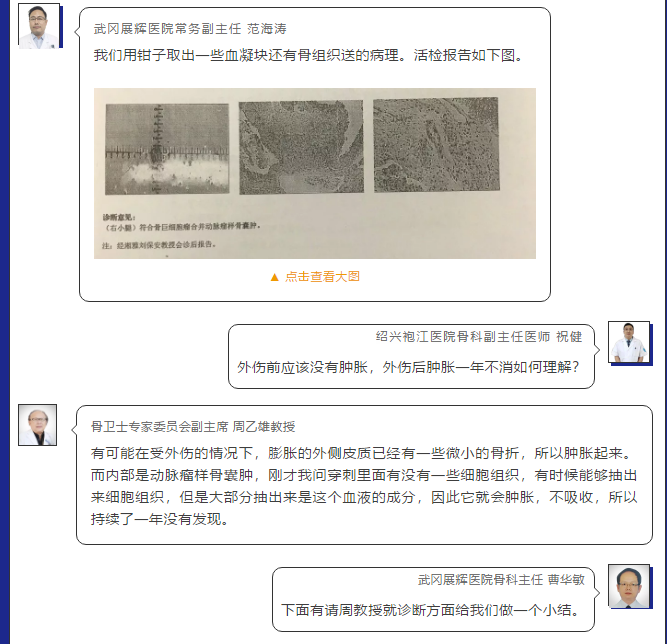

在病例讨论环节,专家们主要围绕病例诊断及治疗两个主题开展精彩讨论,节选如下:

Part 1

Part 2